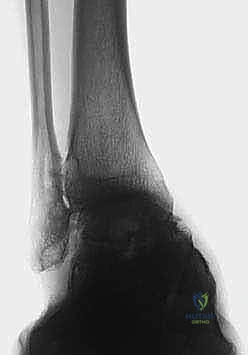

2. التصوير بالأشعة السينية بوضعية الوقوف (Weight-bearing X-rays)

هذا هو حجر الأساس في التشخيص. الأشعة العادية والمريض مستلقٍ لا تظهر الحجم الحقيقي للتشوه. يطلب الدكتور هطيف صوراً خاصة والمريض يحمل وزنه كاملاً على قدميه.

* المنظر الأمامي الخلفي (AP View): لتقييم المسافة المفصلية وتحديد زاوية سطح الساق (Tibial Anterior Surface Angle - TAS).

* منظر سالتزمان (Saltzman View): وهو منظر إشعاعي متخصص جداً لتقييم محاذاة الكعب الخلفي بالنسبة لمحور الساق، وهو أمر حاسم في التخطيط الجراحي.

فهم خشونة مفصل الكاحل من النوع التقوسي (Varus Ankle Osteoarthritis)

خشونة مفصل الكاحل من النوع التقوسي هي حالة مرضية تدريجية (Progressive) لا تحدث بين عشية وضحاها. إنها تتميز بتشوه تقوسي مع فتح أمامي للسطح المفصلي في الطرف البعيد من عظم الساق. وغالباً ما تظهر هذه الحالة بشكل ثنائي (في كلا الكاحلين)، وتكون أكثر شيوعاً لدى النساء في منتصف العمر وكبار السن، وكذلك لدى الرياضيين السابقين أو الأشخاص الذين تعرضوا لإصابات قديمة.